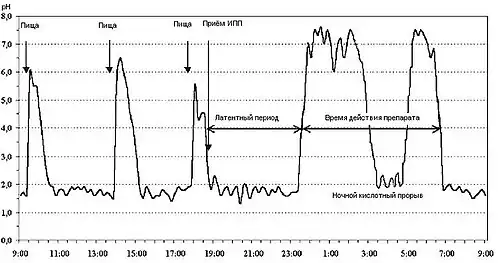

Внутрижелудочная pH-метрия играет важнейшую роль при диагностике и лечении кислотозависимых заболеваний, при исследовании гастроэзофагеальных, дуоденогастральных, фаринголарингеальных рефлюксов. В клинической практике нашли применение несколько методов внутрижелудочной pH-метрии:эндоскопическая (длительность измерений 5 минут), экспресс-pH-метрия (около 30 минут), кратковременная стимулированная (до 2—3 часов) и длительная (24 часа и более) pH-метрия. pH-метрия также применяется для оценки действия кислотоподавляющих препаратов. Измерения выполняется с помощью специальных pH-метрических зондов, вводимых пациенту перорально (при кратковременной pH-метрии), трансназально (при суточной pH-метрии)[21][23], через инструментальный канал эндоскопа (при эндоскопической pH-метрии)[24] или с помощью прикрепляемых к стенке пищевода pH-метрических капсул[25]. Исследование некислых рефлюксов выполняется с помощью импеданс-pH-метрии пищевода[26]. Для дифференциальной диагностики загрудинных болей неясной этиологии применяется гастрокардиомониторинг — одновременное исследование кислотности ЖКТ и электрокардиограммы[21].

24-х часовая pH-метрия пищевода (фрагмент pH-граммы больного ГЭРБ) pH-грамма желудка при подборе ингибиторов протонной помпы

pH-грамма желудка при подборе ингибиторов протонной помпы Прикрепляемая к стенке пищевода капсула «Bravo» для исследования ГЭР